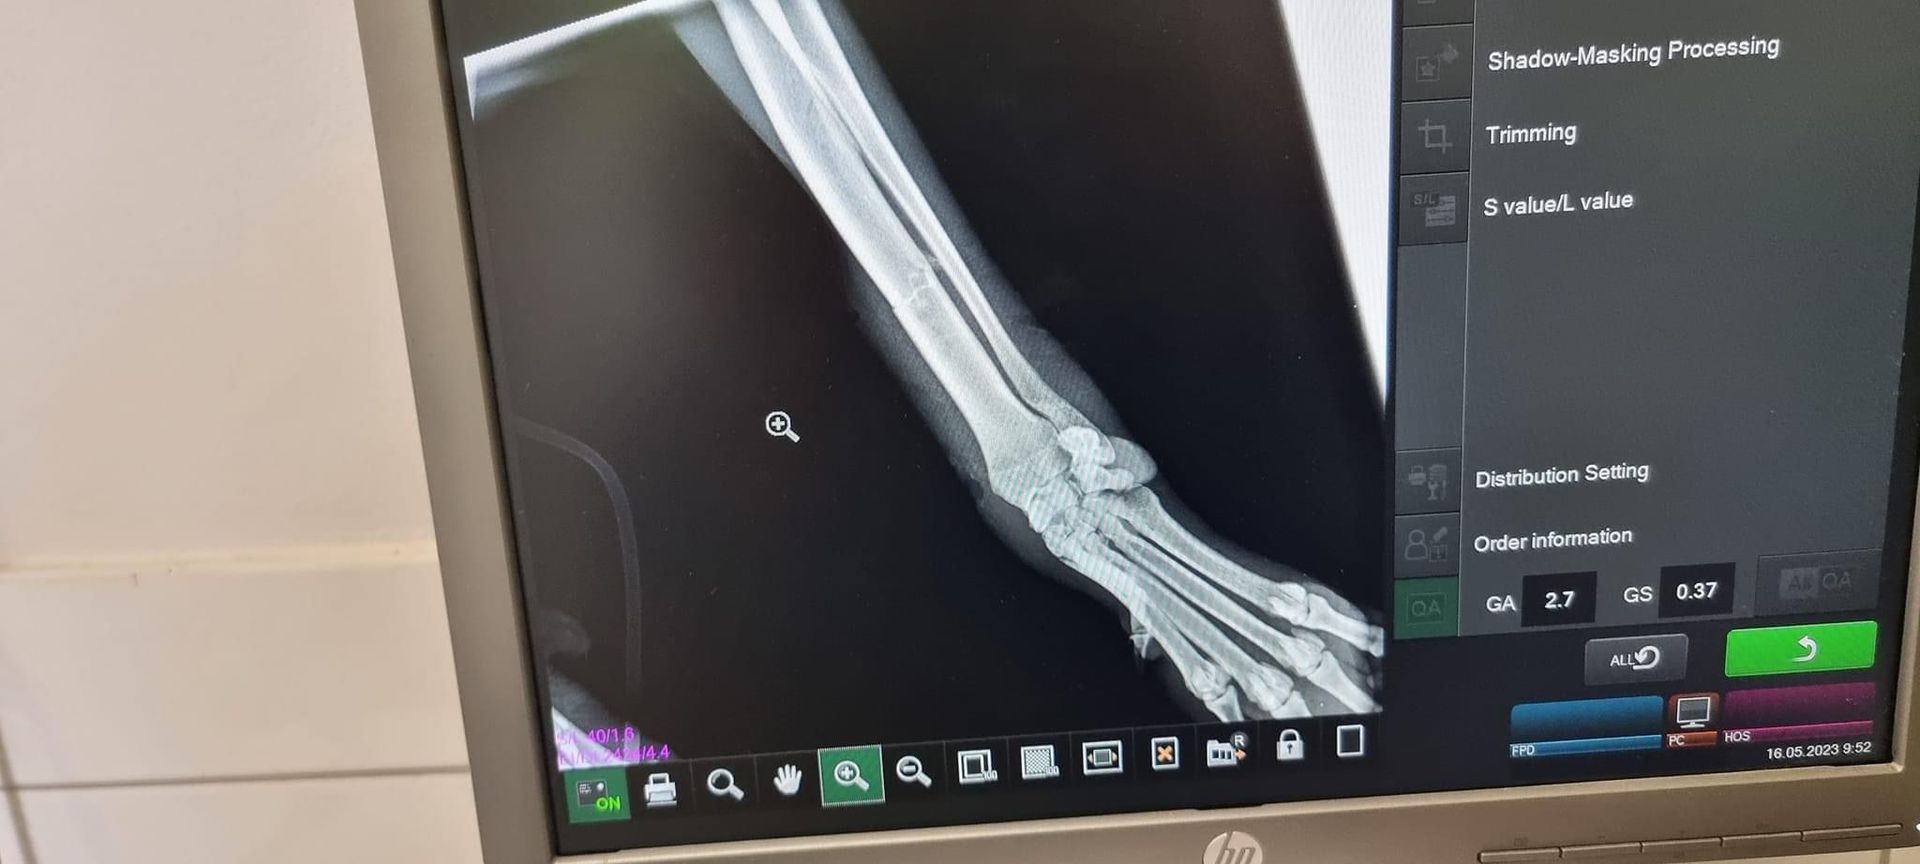

Ausgesetzter Jagdhund an einer stark befahrenen Straße,

Sie sind meistens sehr änsglich, weil ihnen schlimmes angetan wurde.

Unser Tierschützer gab Ihr Futter um Ihr Vertrauen zu gewinnen.

Leider lief sie weg. Er wollte es später nochmal versuchen,

leider wurde sie in der Zwischenzeit angefahren,

schwer Verletzt und liegen gelassen....

Unser Tierschützer brachte sie sofort zum Tierarzt.

Laut neuestem Stand hat sie ein gebrochenes Bein und innere Blutungen.

Wir hoffen das Beste für Sie.

Röntgen Aufnahmen